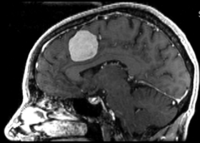

Intra-subject Brain MRI: axial T1 Tumor Growth Assessment

this is the fixed reference image. All images are aligned into this space lleft this is the moving image. The transform is calculated by matching this to the reference image

fixed image/target moving image

This is a typical case of change assessment. We want to know if/how the tumor changed since last exam.

MRI, brain, head, intra-subject, T1, tumor growth, meningioma, change assessment

• reference/fixed : T1 SPGR , 0.9375 x 0.9375 x 1.4 mm voxel size, axial, RAS orientation.

• moving: T1 SPGR , 0.9375 x 0.9375 x 1.2 mm voxel size, sagittal, RAS orientation.